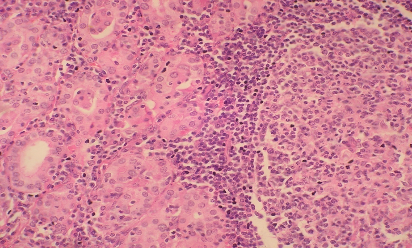

HISTOPATHOLOGY

Section H and E x400. Mass in the wall of the small intestine in a 72 year old male patient who presented with frequent diarrhoea. Make you diagnosis.